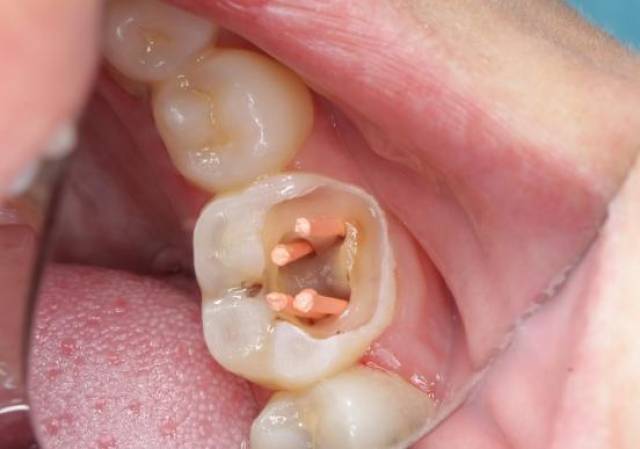

根管治疗全过程是怎么样的?,杀牙神经

图片尺寸552x387